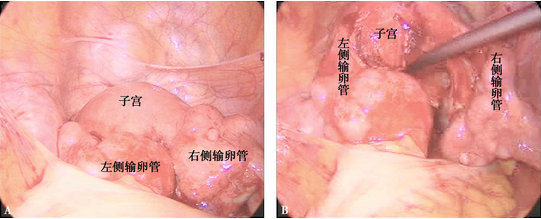

腹腔镜诊断盆腔炎性疾病

A.双侧输卵管壁水肿;B.双侧输卵管表面明显充血、右侧输卵管迂曲、粘连。